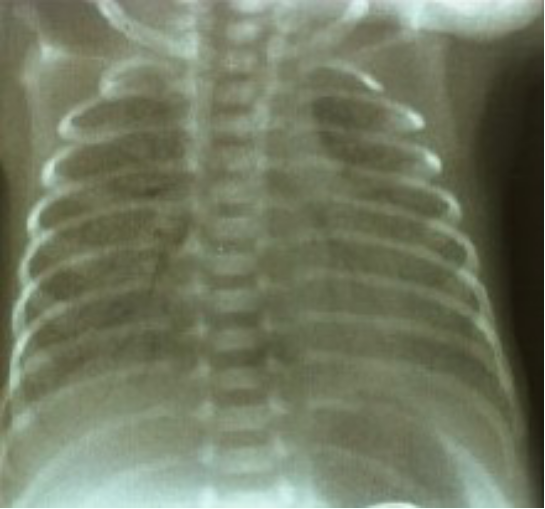

X线胸片

广泛肺不张(diffuse bilateral atelectasis)

透亮度减低,毛玻璃(groun-glass appearance)

颗粒网状阴影(granular-reticular appearance)

支气管充气征(air bronchograms)

groun-glass,granular-reticular appearance

No air bronchograms

Grade II-III RDS